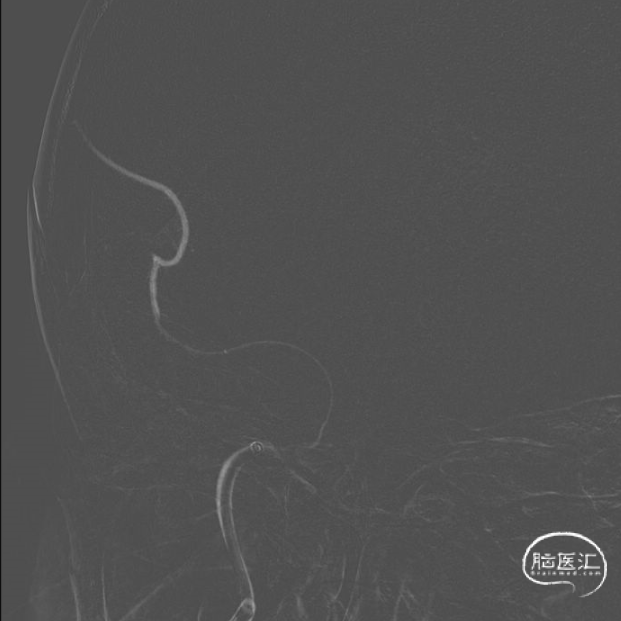

弓造影:主动脉弓II型。

左椎造影:左侧椎动脉全程走形严重迂曲,基底动脉纤细。

右颈造影:右侧颈内动脉C1、C6-C7段走形迂曲,C4-C7段管腔欠光滑,C4后膝部可见一宽颈瘤样突起(颈7.55mm,长3.32mm),C4段前膝、C7段轻度狭窄,约10%;右侧大脑中动脉M1段走形迂曲,管壁欠光滑,M1远端中度狭窄,约50%,M1近端可见一宽颈瘤样突起(颈5.17mm,长1.35mm);右侧大脑前动脉A1-A2段走形迂曲,前交通开放,向右侧大脑前动脉供血。

右椎造影:右侧椎动脉全程走形迂曲,管腔光滑,管腔未见明显狭窄及斑块。